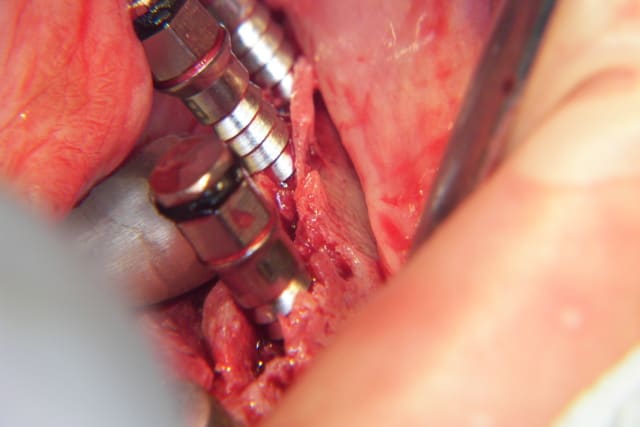

noahaxeltiger-olivier

17/03/2009 à 00h17

Effectivement Growler, la crête atrophique à la mandibule est souvent dense (type 1 à 2); il est difficile réaliser une mobilisation du volet vestibulaire avec les seuls osteotomes. Pour augmenter l'élasticité du volet osseux vestibulaire, une incision longitudinale basale de décharge es très souvent nécessaire en plus des incisions verticales et crestale. Cette incision longitudinale augmente la résilience et soulage la mobilisation du volet osseux vestibulaire. Ce dernier peut très facilement après mobilisation être transvissé et fixé par des vis d'osteosynthèses classiques.

Il est à mon avis préférable d'obtenir un trait de fracture propre et maitrisé plutôt qu'un volet vestibulaire fragilisé, traumatisé et abimé.

Splitting mandibulaire nnrckm - Eugenol